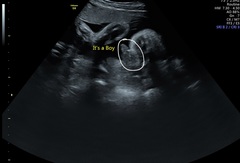

@stairgates nub theory is just a theory with no actual evidential basis. It would be such a waste of money to have a private scan at 13 weeks just to get pictures of the nub when you could wait a few weeks and actually know for sure. My NHS 12 week scan was at 13 weeks and I got a really clear nub picture. All the 'experts' said definitely girl. It was completely flat (see pic). Luckily I just did it for a laugh and knew it was a 50/50 guess. I'm having a boy which has been confirmed at 3 scans now!

Can they really tell the gender at 14 weeks?

bluemoon, I would have guessed girl for you too!Grin Was yours taken from a video or just a one off shot? If your lucky enough to get a video then it shows alot more than one angle and catches bits that arent always caught. If op can afford the video at 13 weeks then its worth looking into even just for the fun aspect :)